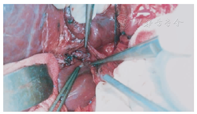

患儿仰卧位,原上腹肋缘下切口;稍微分离切口下粘连;行小肠系膜静脉的二级血管穿刺置管,测压和造影检查,了解门静脉的病变情况;将肝脏的镰状韧带和右侧三角韧带游离;游离肝门的了解原搭桥血管的形态;将胆囊从胆囊床上游离,保留胆囊血管和胆囊壁完好无损;沿着门静脉右支的走行方向劈开Gallison鞘,在其后方找到门静脉的右支,沿着静脉壁向左右游离,至少2 cm长度(图1),必要时沿着门静脉右支的表面将肝裂劈开以延长静脉的游离长度;穿刺门静脉,测压和造影;切开肝十二指肠韧带外侧壁表面的腹膜,在其内找到梗阻近端粗大门静脉的主干,游离静脉的前壁放置血管侧壁阻断钳。根据测量门静脉主干至肝门静脉右支之间的距离,截取肠系膜下静脉,其直径要在5 mm以上。首先用侧壁钳阻断门静脉右支的前壁,根据搭桥血管的直径纵行切开静脉壁,将搭桥血管的向心端与门静脉右支端侧吻合;然后将搭桥血管的远心端与门静脉主干的侧壁端侧吻合,吻合均采用7-0 prolene线间断缝合(图2)。吻合后做门静脉的测压和造影,术中超声了解搭桥血管的通畅情况。